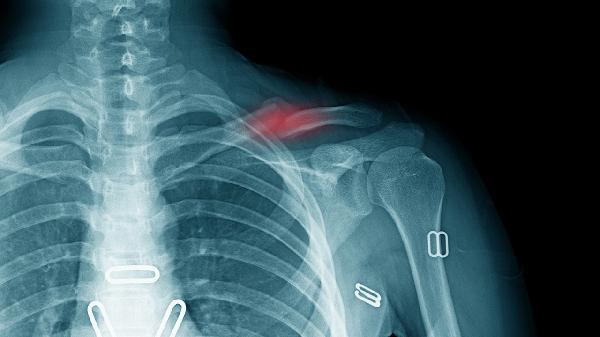

冠状动脉供血不足可能诱发运动相关性心绞痛。疼痛常位于胸骨后部,伴随压迫感并向左肩放射。需遵医嘱使用硝酸甘油片或单硝酸异山梨酯缓释片改善血流,配合阿托伐他汀钙片调节血脂。心电图与冠脉造影是明确诊断的主要手段。

肺部感染或结核可能继发胸膜炎症。疼痛呈刀割样,咳嗽时加剧,可能伴有低热症状。确诊需通过胸部CT检查,治疗可选用头孢克肟分散片抗感染,联合乙酰氨基酚片镇痛。胸腔积液量多时需穿刺引流。